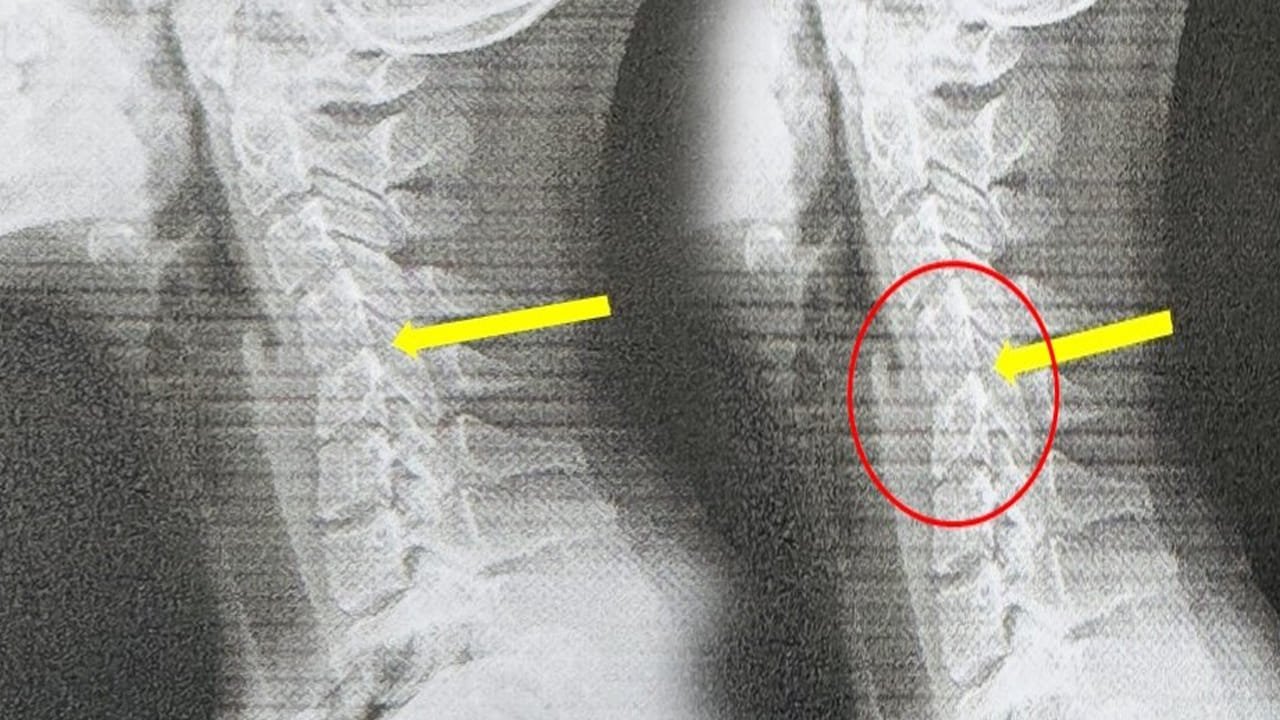

20 ఏళ్ల యువతి అతిగా ఫోన్ వాడటం వల్ల.. ఆమె మెడ 60 ఏళ్ల వృద్దుడిలా మారిపోయింది. ఆమెకు టెస్టులు చేసిన వైద్యులు.. అతిగా ఫోన్ వాడటం వల్ల ఇది జరిగిందని నిర్ధారణకు వచ్చారు. తనకు తరచూ తలనొప్పి వచ్చేదని.. మెడ రాయిలా మారిపోవడమే కాదు.. వలిపోయిందని డాక్టర్కు చెప్పుకొచ్చింది. హుటాహుటిన డాక్టర్లు CT స్కాన్ తీయగా.. అందులో షాకింగ్ విషయం వెల్లడైంది. ఆమె గర్భాశయ వెన్నుముక తన సహజ ఆకృతిని కోల్పోగా.. కొన్ని ప్రాంతాల్లో వెన్నుపూస జారిపోయిన సంకేతాలు కూడా డాక్టర్లు గుర్తించారు.

‘టెక్స్ట్ నెక్’ అని పిలిచే ఆమె పరిస్థితి.. అకాల గర్భాశయ క్షీణతకు ముందస్తు హెచ్చరిక అని తెలిపారు. తైవాన్ డాక్టర్ ఈమేరకు మాట్లాడుతూ.. ఆమె పరిస్థితి.. ఇప్పుడున్న యువత ఎదుర్కుటోందని చెప్పుకొచ్చారు. ‘ప్రతిరోజూ గంటల తరబడి ఫోన్లు చూస్తూ, షోలు చూస్తూ, ఆటలు ఆడుతూ గడిపారు. కానీ వారి శరీరాలు నొప్పితో కేకలు వేసే వరకు, సమస్య తీవ్రతను గుర్తించలేకపోయారు.’ అని అన్నారు.

మెడను 60 డిగ్రీలు వంచడం సాధారణ స్మార్ట్ఫోన్ భంగిమ.. ఇది గర్భాశయ వెన్నెముకపై దాదాపు 27 కిలోల భారాన్ని మోపుతుందని డాక్టర్ యే వివరించారు.ఇది ఒక భారీ బౌలింగ్ బంతిని లేదా ఎనిమిదేళ్ల పిల్లవాడిని మీ మెడపై ఎక్కువసేపు వేలాడదీయడం లాంటిది అని అన్నారు. ‘కాలక్రమేణా, మెడ కండరాలు, స్నాయువులు తట్టుకోలేవు. డిస్క్లు క్రమంగా కుదించబడతాయి. మొత్తం గర్భాశయ నిర్మాణం ఆకృతిని కోల్పోతుంది’.